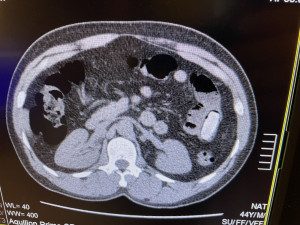

„Pětačtyřicetiletý cizinec cestoval linkovým autobusem na trase Brusel – Praha, přičemž cílovou destinací mělo být Rakousko. Při celní kontrole na něj pozitivně reagoval služební pes vycvičený na vyhledávání drog, označil ho a muž byl pro podezření přepraven do zdravotnického zařízení. Následné rentgenové vyšetření prokázalo výskyt cizích předmětů v tělních dutinách cestujícího a laboratorní rozbory potvrdily podezření celníků, že se jedná o kokain,“ informovala Hana Prudičová, mluvčí Generálního ředitelství cel.